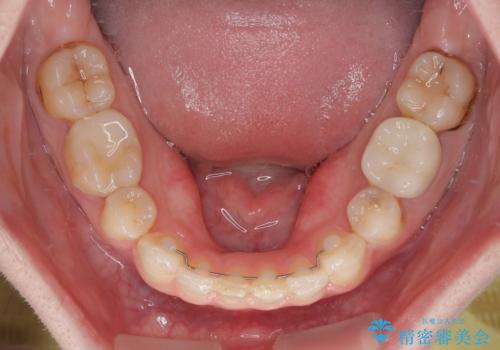

- 前歯のデコボコと、その結果むし歯が進行していることを気にして来院された患者様です。

前歯や奥歯の根管治療を行い、その後上下左右の第一小臼歯4本を抜歯してワイヤー装置にて矯正治療を行うこととしました。

矯正治療後には、根管治療を行った歯をオールセラミッククラウンにて補綴治療を行うこととしました。

治療途中で激務の会社に就職することとなり、なかなか矯正治療に通院することができなくなり、治療期間が想定の2倍近くとなりましたが、無事に満足のいく形で治療を終えることができました。